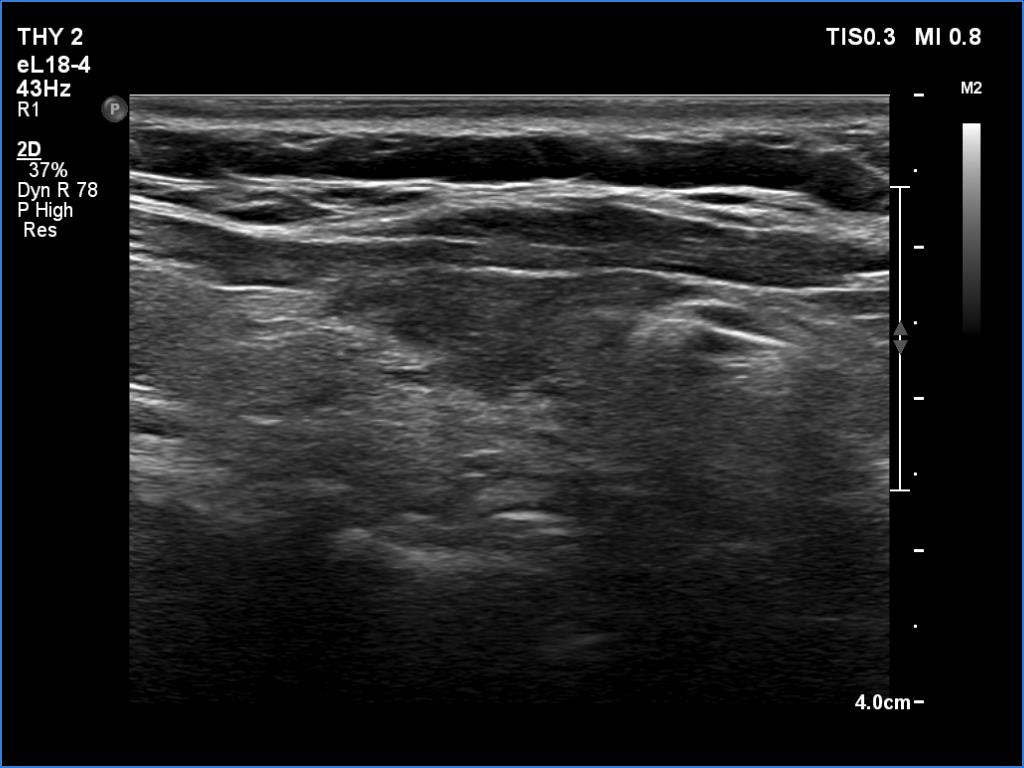

Ultrasonography. The thyroid was atrophic. Both lobes were composed of a central, larger hypoechoic area surrounded with echonormal tissue. The pattern did not correspond to nodule. The vascularity was decreased.

Comment. A central hypoechoic part surrounded with echonormal tissue is one of the typical presentations of Hashimoto's thyroiditis, not infrequently misinterpreted as a large hypoechoic nodule which occupies great part of a lobe. The irregular margins, the infiltrative borders of the thyroiditis are the main clues of differentiation this presentation from nodular goiter. The pattern can be observed usually in both lobes which is also characteristic of this form of thyroiditis.